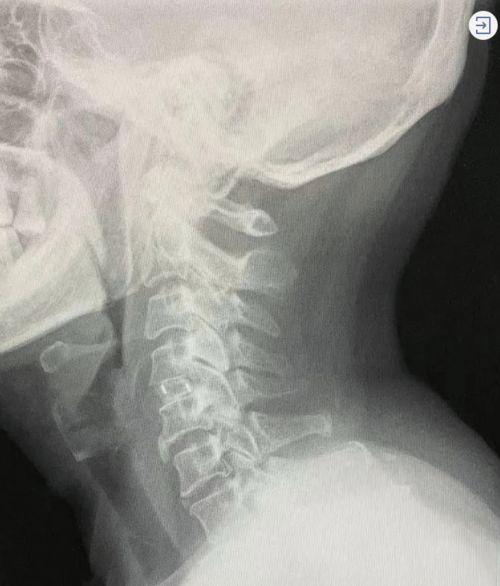

颈椎微创手术,顾名思义,就是通过微小切口进行的颈椎手术。与传统手术相比,它具有创伤小、恢复快、疼痛轻等优点。近年来,随着医疗技术的不断发展,颈椎微创手术越来越受到患者的青睐。

颈椎微创手术主要是通过在颈椎部位开一个小孔,将手术器械伸入,对病变部位进行切除或修复。这种手术方式可以最大限度地减少对周围组织的损伤,从而降低术后并发症的发生率。

为了让大家更直观地了解颈椎微创手术的过程,下面我将为大家分享一段颈椎微创手术的视频。请注意,以下内容可能引起不适,请谨慎观看。

(此处插入颈椎微创手术视频)